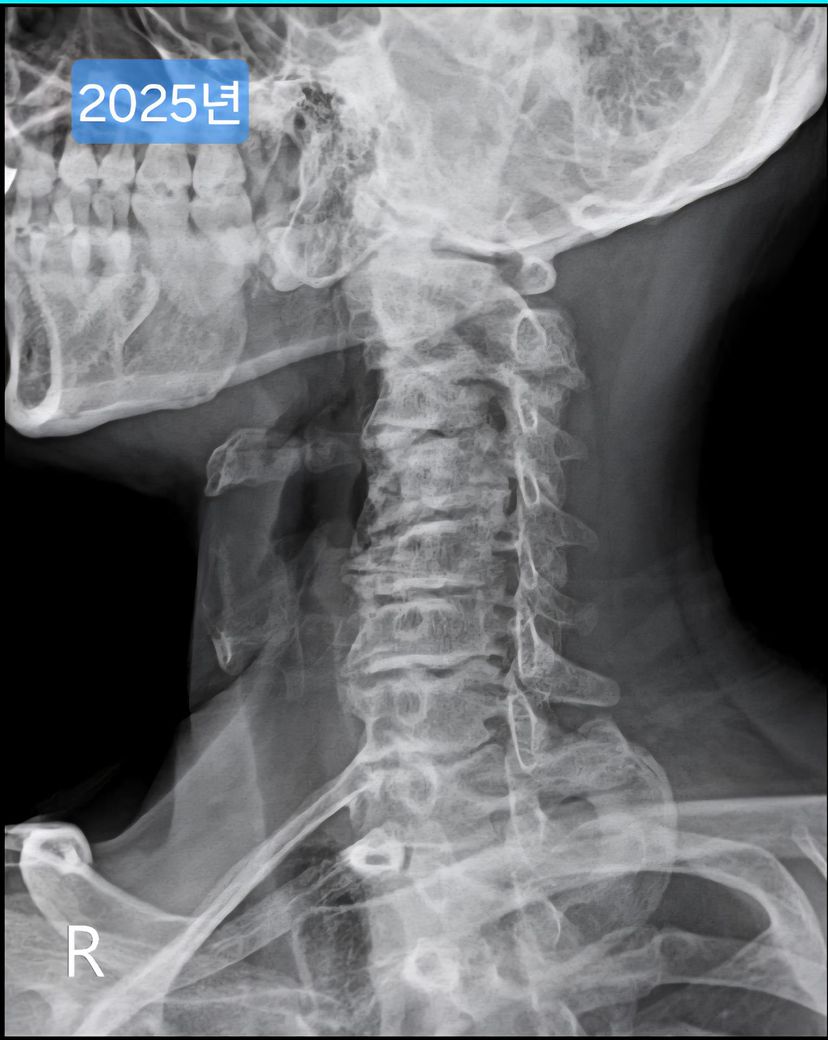

목이 일자목, 경추사이 공간 좁음 등 형태가 안 좋은데요.

여러 방도로 제 목 엑스레이 사진을 보여드리면

현재 목의 형태가 안 좋은건 충분히 알겠는데.

• 1번 째 사진

• 2번 째 사진

• 3번 째 사진

• 4번 째 사진